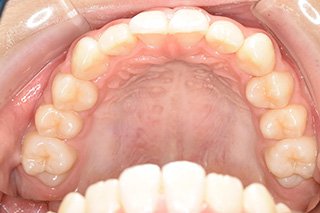

顎顔面矯正症例 11歳女児 Case

| 主訴 | 永久歯が変な所からはえてきている|顔貌 | |

|---|---|---|

| 施術内容 | 矯正1期治療 | |

| 治癒期間 | 1年5ヶ月間 | |

| 費用 | 459,200円(税込) | |

| リスク・ 副作用 | 痛みを伴う | |